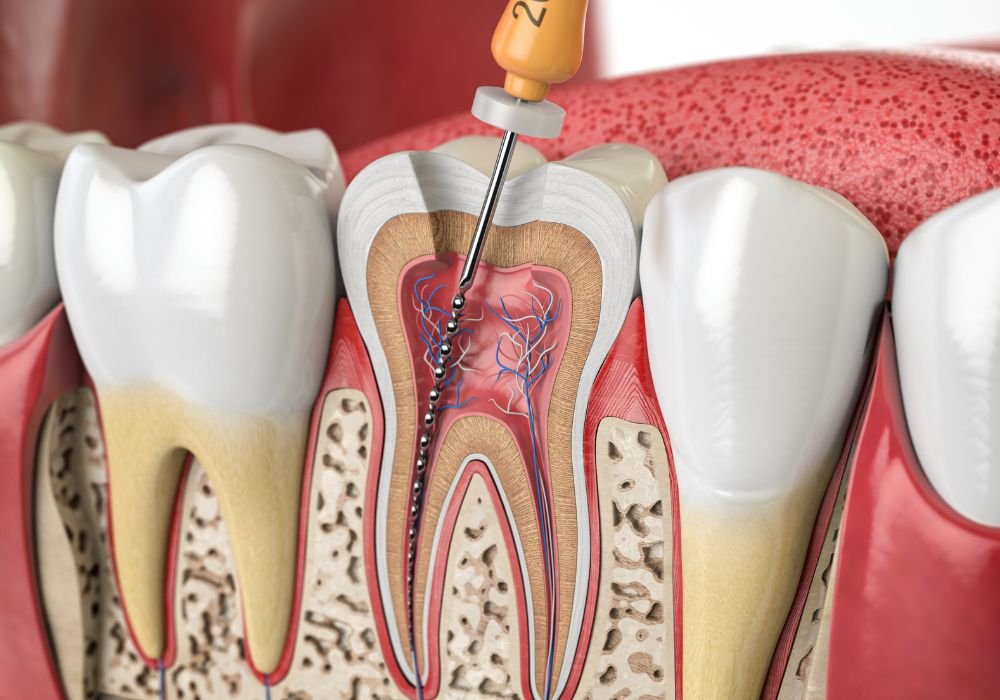

L’endodontie traite les infections de la pulpe dentaire afin de sauver la dent naturelle. Lorsque la carie atteint le nerf, un traitement canalaire est nécessaire pour éliminer l’infection et préserver la structure dentaire.

Un retraitement peut être indiqué en cas d’échec d’un ancien traitement. Les urgences pulpaire et péri-apicales sont prises en charge rapidement pour soulager la douleur.

Sauver la dent est toujours préférable à son extraction.